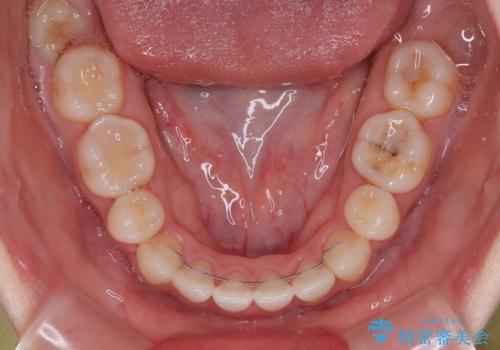

- 口元の突出感と上下前歯のズレを気にして来院された患者様です。

舌の突出癖により上下の前歯は非接触となっている状態でした。

舌のトレーニングを行わないと上下前歯の接触達成は困難であるため、トレーニングをしっかりと行っていただきながら、治療を進めて行くこととしました。

突出感改善のため、上下左右の第一小臼歯4本を抜歯し、ワイヤー装置にて矯正治療を行うこととしました。

舌のトレーニングをしっかりと行ってくださり、予定通りの期間で理想的な仕上がりを達成することができました。